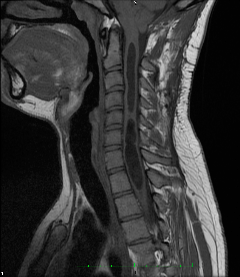

Obraz z przed i po Sekcji Filum Terminale

Przecięcie filum terminale służy usunięciu napięcia i zahamowaniu rozwoju chorby. Objawychoroby Chiari I są spowodowane przez obumieranie tkanek mózgowych poddanych dużej sile nacisku. Po przecięciu filum terminale, mimo że rezonans pozornie nie wykazuje zmian, napięcie i ucisk w otworze potylicznym znikają. Ukrwienie w miejscu dotkniętym chorobą poprawia się i wraz z nim maleją objawy powodowane przez ucisk.

W przypadku syndromu Chiari I, siringomieli i skoliozy przecięcie filum terminale zatrzymuje rozwój choroby. Torbiel która powstała w wyniku obumarcia komórek nerwowych nie zmienia się, ale może zniknąć w momencie gdy przestrzeń która otacza rdzeń kręgowy spontanicznie się otworzy. To nie znaczy że choroba została wyleczona, jedynie że torbiel sie opróżniła. Symptomy tej choroby są wynikiem obumierania komórek nerwowych z czego powstaje torbiel w postaci guza. Przecięcie filum terminale ma trzy zalety: zatrzymuje obumieranie komórek nerwowych, odbudowuje komórki które nie funkcjonowały ale nie obumarły oraz zmniejsza efekt guzowatości torbieli poprzez rozluźnienie w rdzeniu kręgowym.